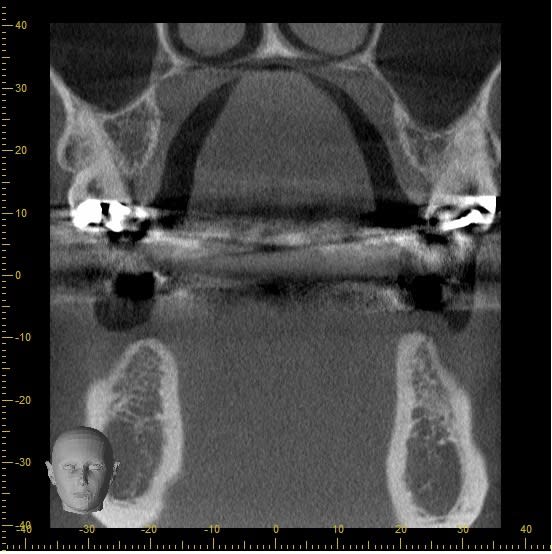

Salut ploukinette tu fais une erreur dans ta lecture de ton scan, tu as fait une coupe frontale, ce qui peut ne pas correspondre à l'axe de la mandibule au niveau de ta 46.

Il veut dire que sur ta 2 eme et3 eme coupe, l'axe de la coupe n'est peut être pas perpendiculaire à la mandibule.

En effet, dans la planification implantair, il faut s'assurer que les coupes frontales soient perpendiculaires à la corticale..

Si ce n'est pas perpendiculaire, il y aura déformation et donc image faussée..